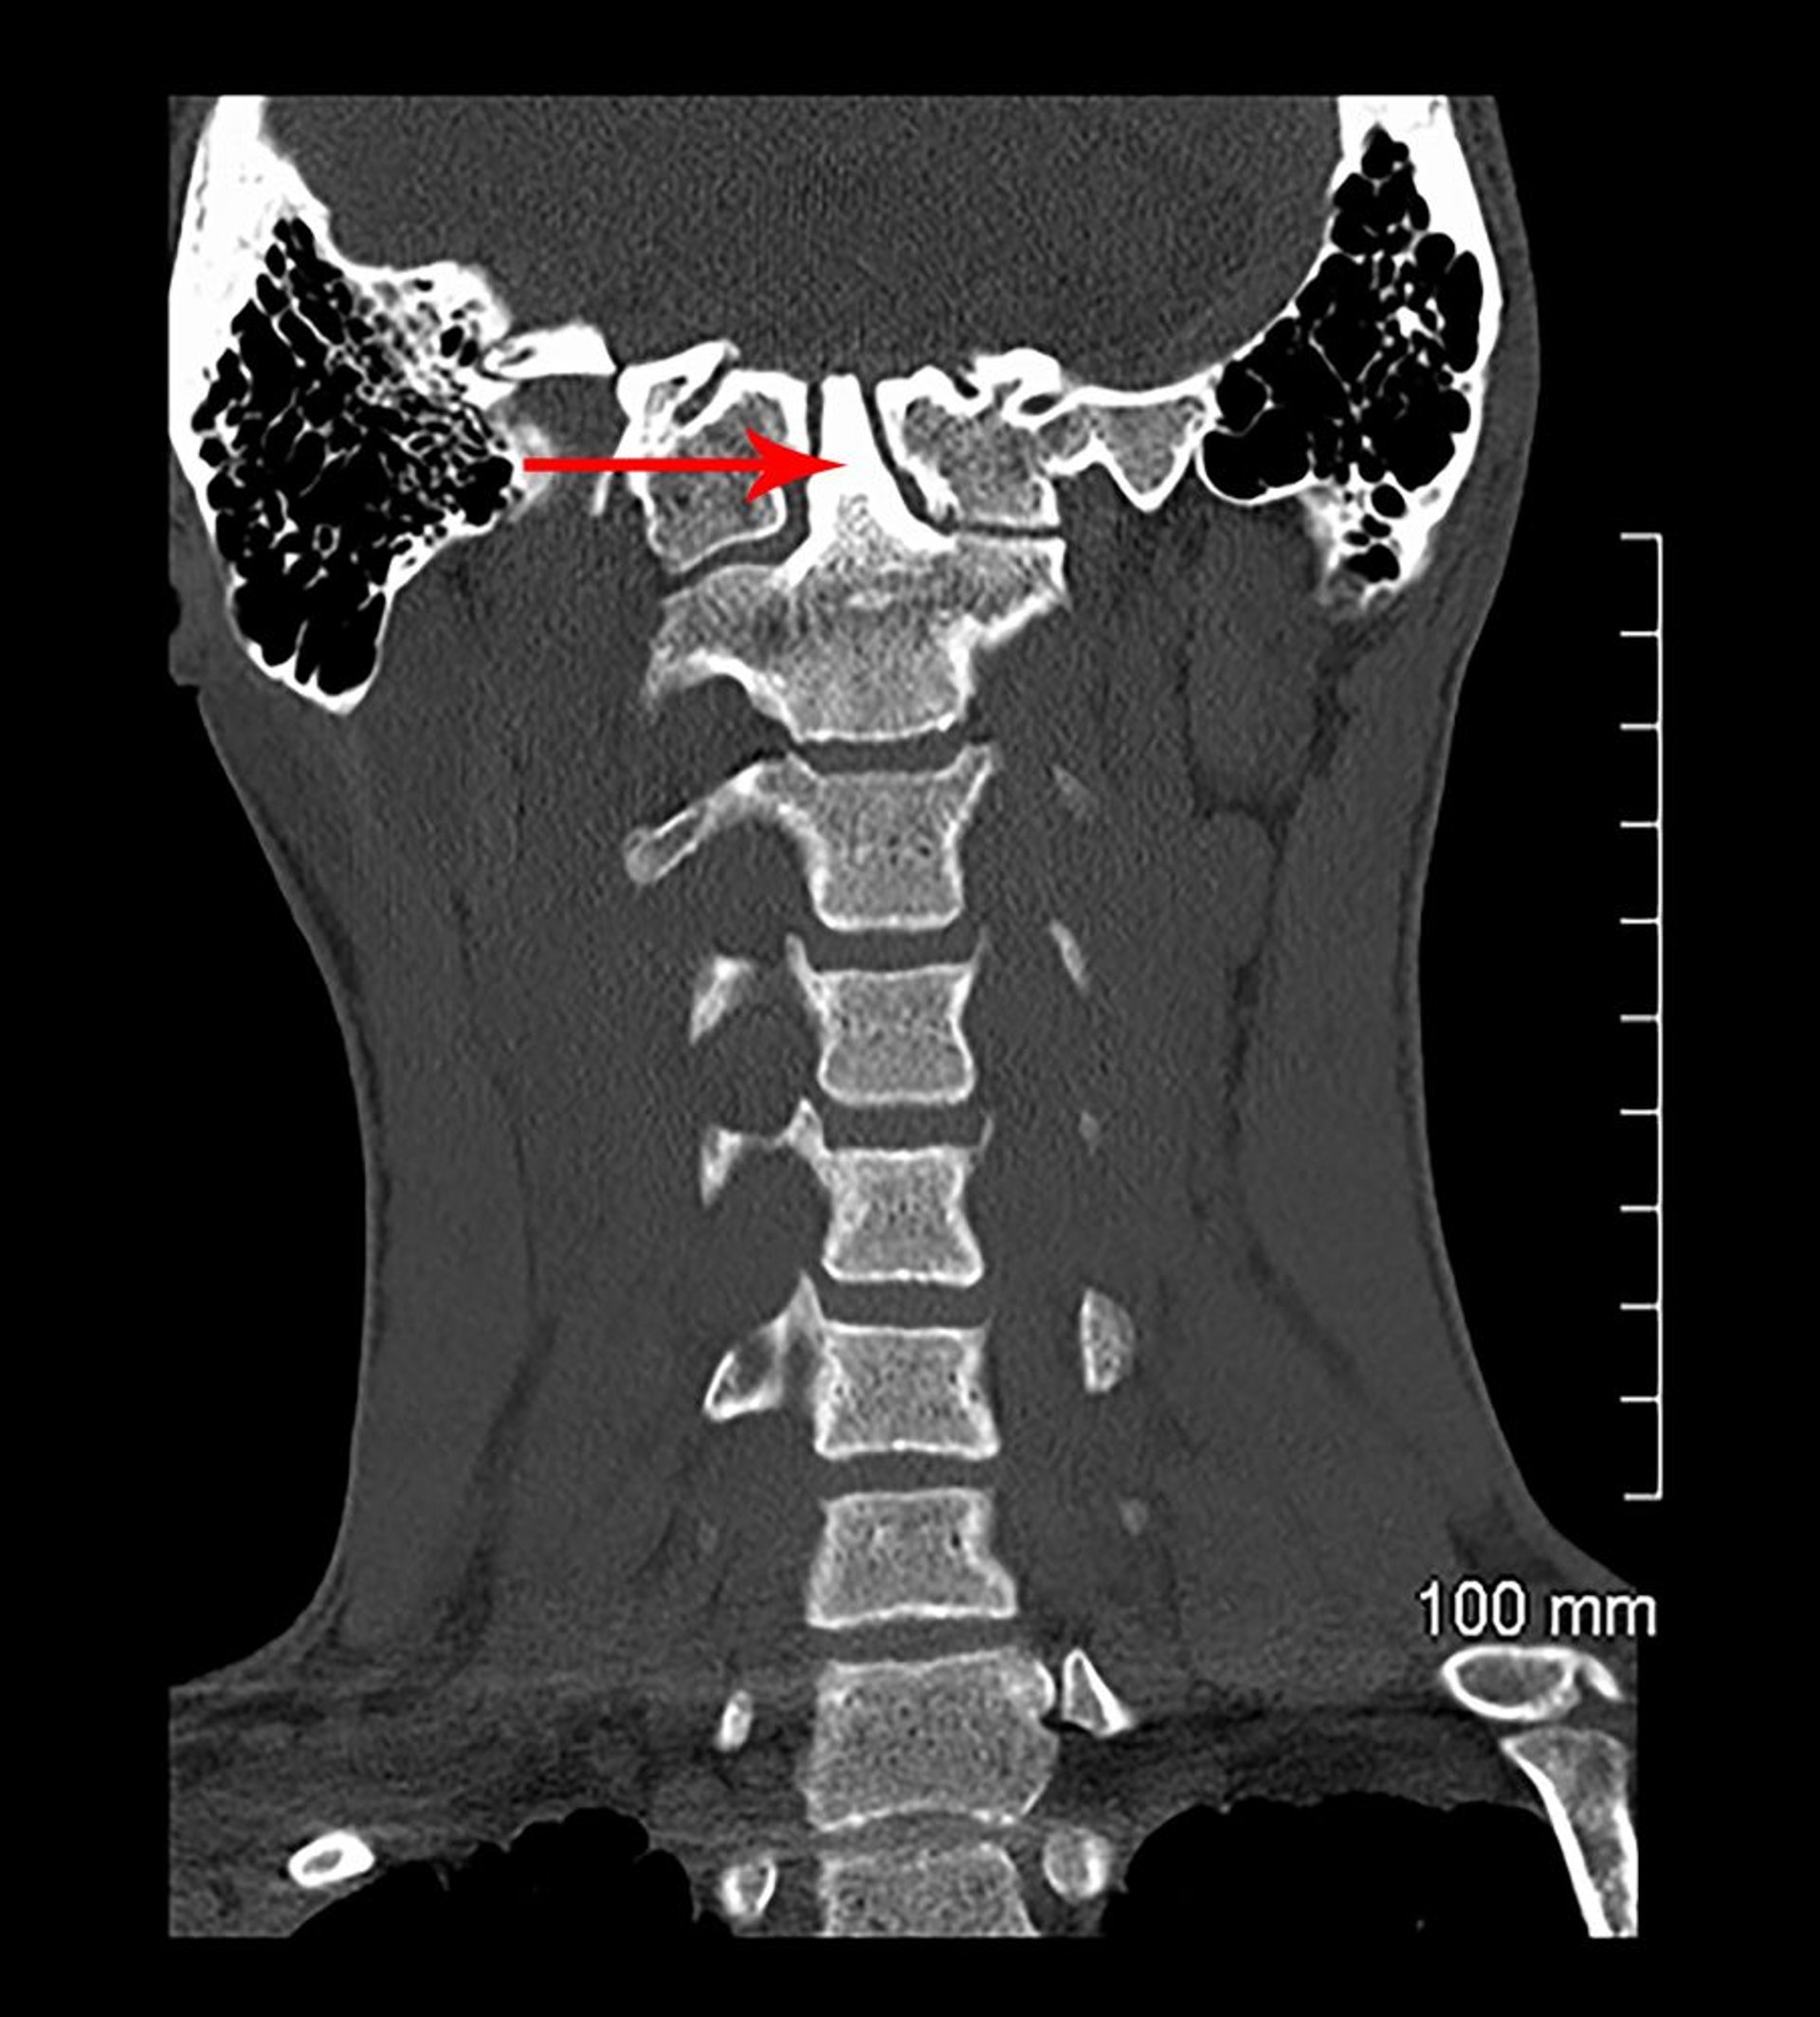

このCT冠状断像では,C1が頭蓋底に融合している(先天性)。歯突起(矢印で示す)は頭蓋底に向かって伸びている(頭蓋底陥入)。